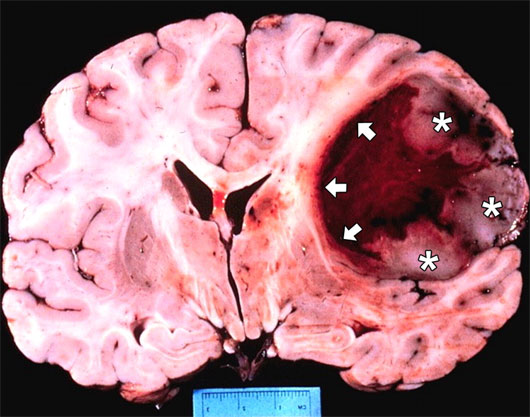

Nhóm nghiên cứu do giáo sư Alessandro Perin thuộc Viện thần kinh học Carlo Besta ở thành phố Milan, Italy, đứng đầu cho biết các protein nói trên có khả năng kích thích và phát triển glioblastoma, một trong những loại u não ác tính phổ biến nhất.

Nhờ các protein này, các tế bào trong glioblastoma phát triển nhanh chóng, lây lan khắp não và chèn lấn các tế bào não thông thường.

Theo giáo sư Perin, hai protein trên hoạt động trong vài nhóm tế bào glioblastoma nhất định, nơi các khối u não bắt đầu sản sinh, và tạo ra tế bào u não đầu tiên. Chúng cũng kích thích sự tái sinh của u não. Điều này giải thích tại sao tỷ lệ u não tái phát sau phẫu thuật và hóa trị hoặc xạ trị thường cao hơn các dạng u khác.